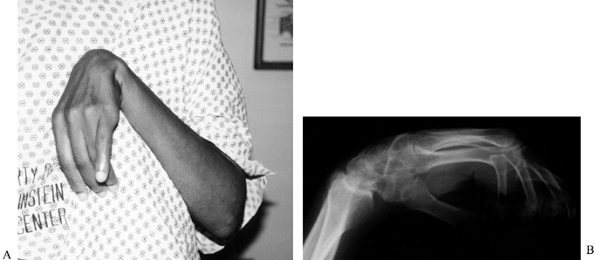

Figure 67.4. Clinical photograph (A) and radiograph (B)

of a patient with severe wrist flexion deformity and subsequent carpal tunnel syndrome from compression of the median nerve against the proximal edge of the transverse carpal ligament. |